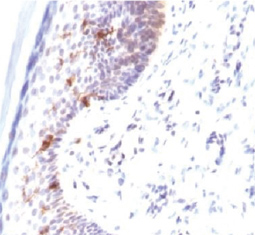

Epidermal cells form the epidermis, the outermost of the three layers that together constitute the skin. Histologically, the epidermis is composed primarily of four tightly adherent layers of squamous epithelium organized into distinct vertical zones by stages of differentiation. From innermost to outermost, the layers are: stratum basale (basal cell layer), stratum spinosum (spinous layer), stratum granulosum (granular layer), and stratum corneum (cornified layer). The epidermis consists largely of keratinocytes (>90%) but also contains melanocytes, Langerhans cells, Merkel cells, and inflammatory cells.

GeneTex is proud to offer an outstanding selection of antibody reagents to study epidermal cells. Please see the highlighted antibodies below.